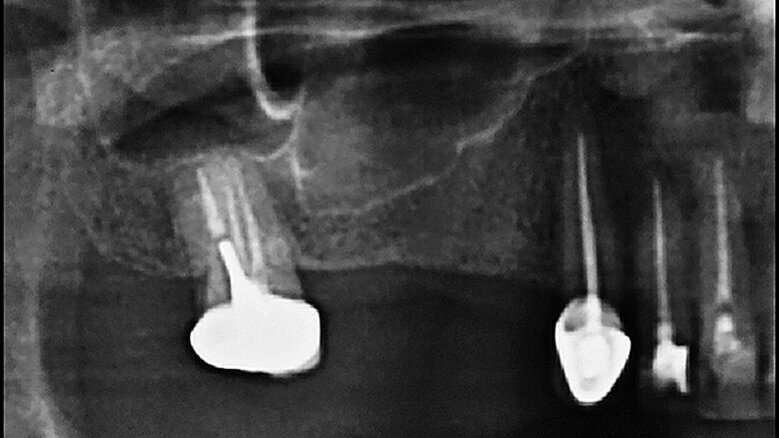

Obr. 1a: RTG snímek bezzubého prostoru znázorňující pneumatizaci čelistní dutiny Obr. 1b: Schéma představující možný klinický vývoj u pacienta a také možnou fluktuaci reziduální výšky alveolárního hřebene. V požadovaném místě implantace, k nahrazení zubu 16, byly naměřeny 4 mm.